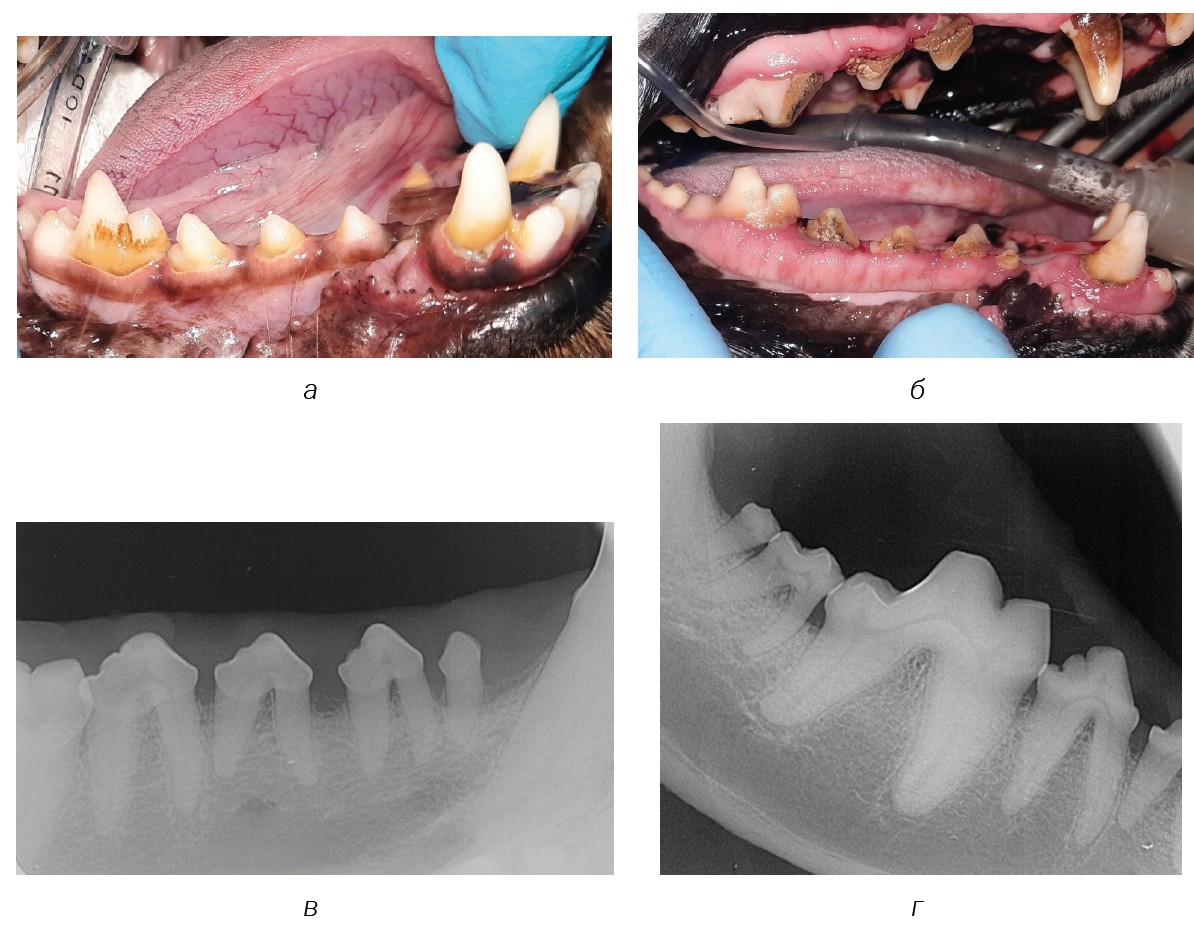

Fig. 6. Dental calculus: a — stage 1 (409 tooth) and stage 3 (404 tooth); б — stage 2 (409–405 teeth); в and г — intraoral radiograph for stage 2 dental calculus.

Source: VTC "Dentalvet".